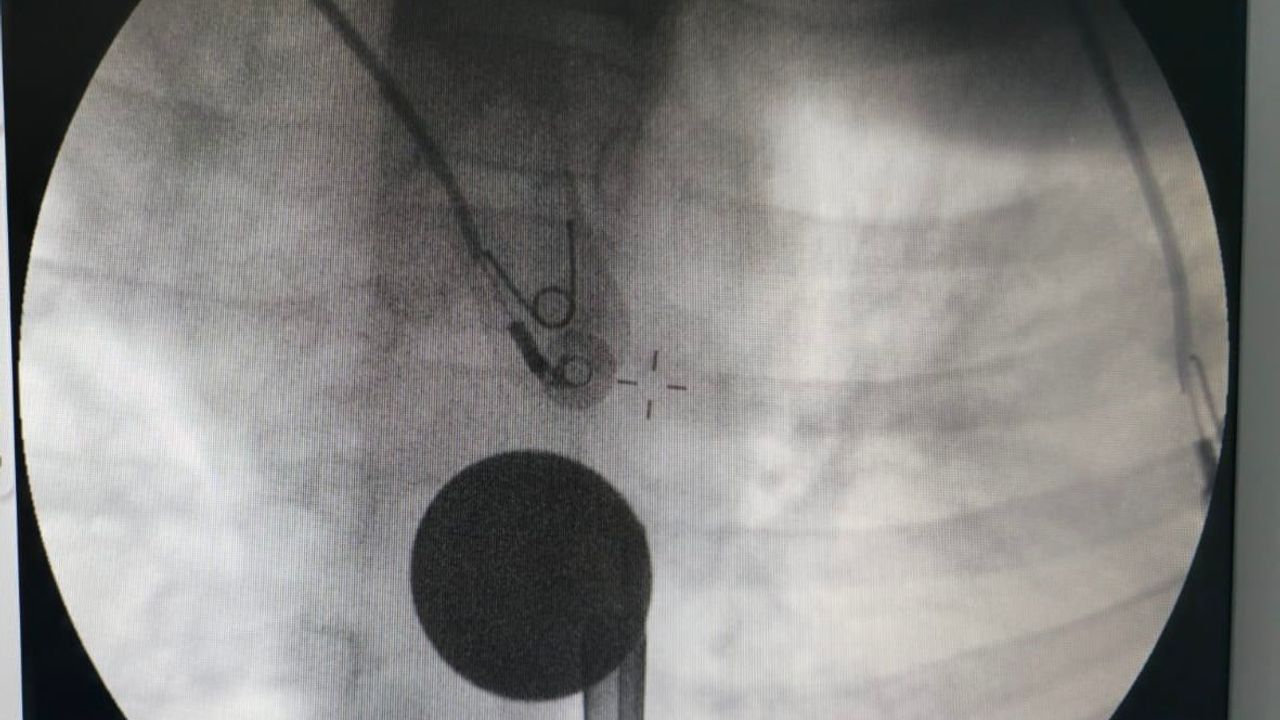

Yabancı cisim yutma şikayetiyle ailesi tarafından Siirt Eğitim ve Araştırma Hastanesine getirilen 8 yaşındaki Y.K., yapılan ilk değerlendirme ve görüntüleme tetkiklerinin ardından ilgili branşlarca operasyona alındı. Y.K.'nın yemek borusuna kadar ilerlediği tespit edilen madeni para, gastroenteroloji uzmanı Dr. Yaren Dirik ve kulak burun boğaz hekimi Yasin Gökçınar tarafından müdahale edilerek çıkartıldı. Operasyonun ardından bir süre gözlem altında tutulan Y.K., tedavisinin tamamlanmasıyla taburcu edildi.

Siirt Eğitim ve Araştırma Hastanesi Başhekim Yardımcısı Uzman Dr. Burak Özkan, çocuk hastalarda yabancı cisim yutma vakalarının ciddi riskler oluşturabileceğini söyledi. Uzm. Dr. Özkan, 'Hastanemize başvuran 8 yaşındaki hastamızın yemek borusuna kaçan madeni para, gastroenteroloji ve KBB ekiplerimizin koordineli ve titiz çalışmasıyla herhangi bir komplikasyona yol açmadan başarılı bir şekilde çıkarılmıştır. Operasyon süreci sorunsuz geçmiş olup hastamızın genel durumu iyidir' dedi.